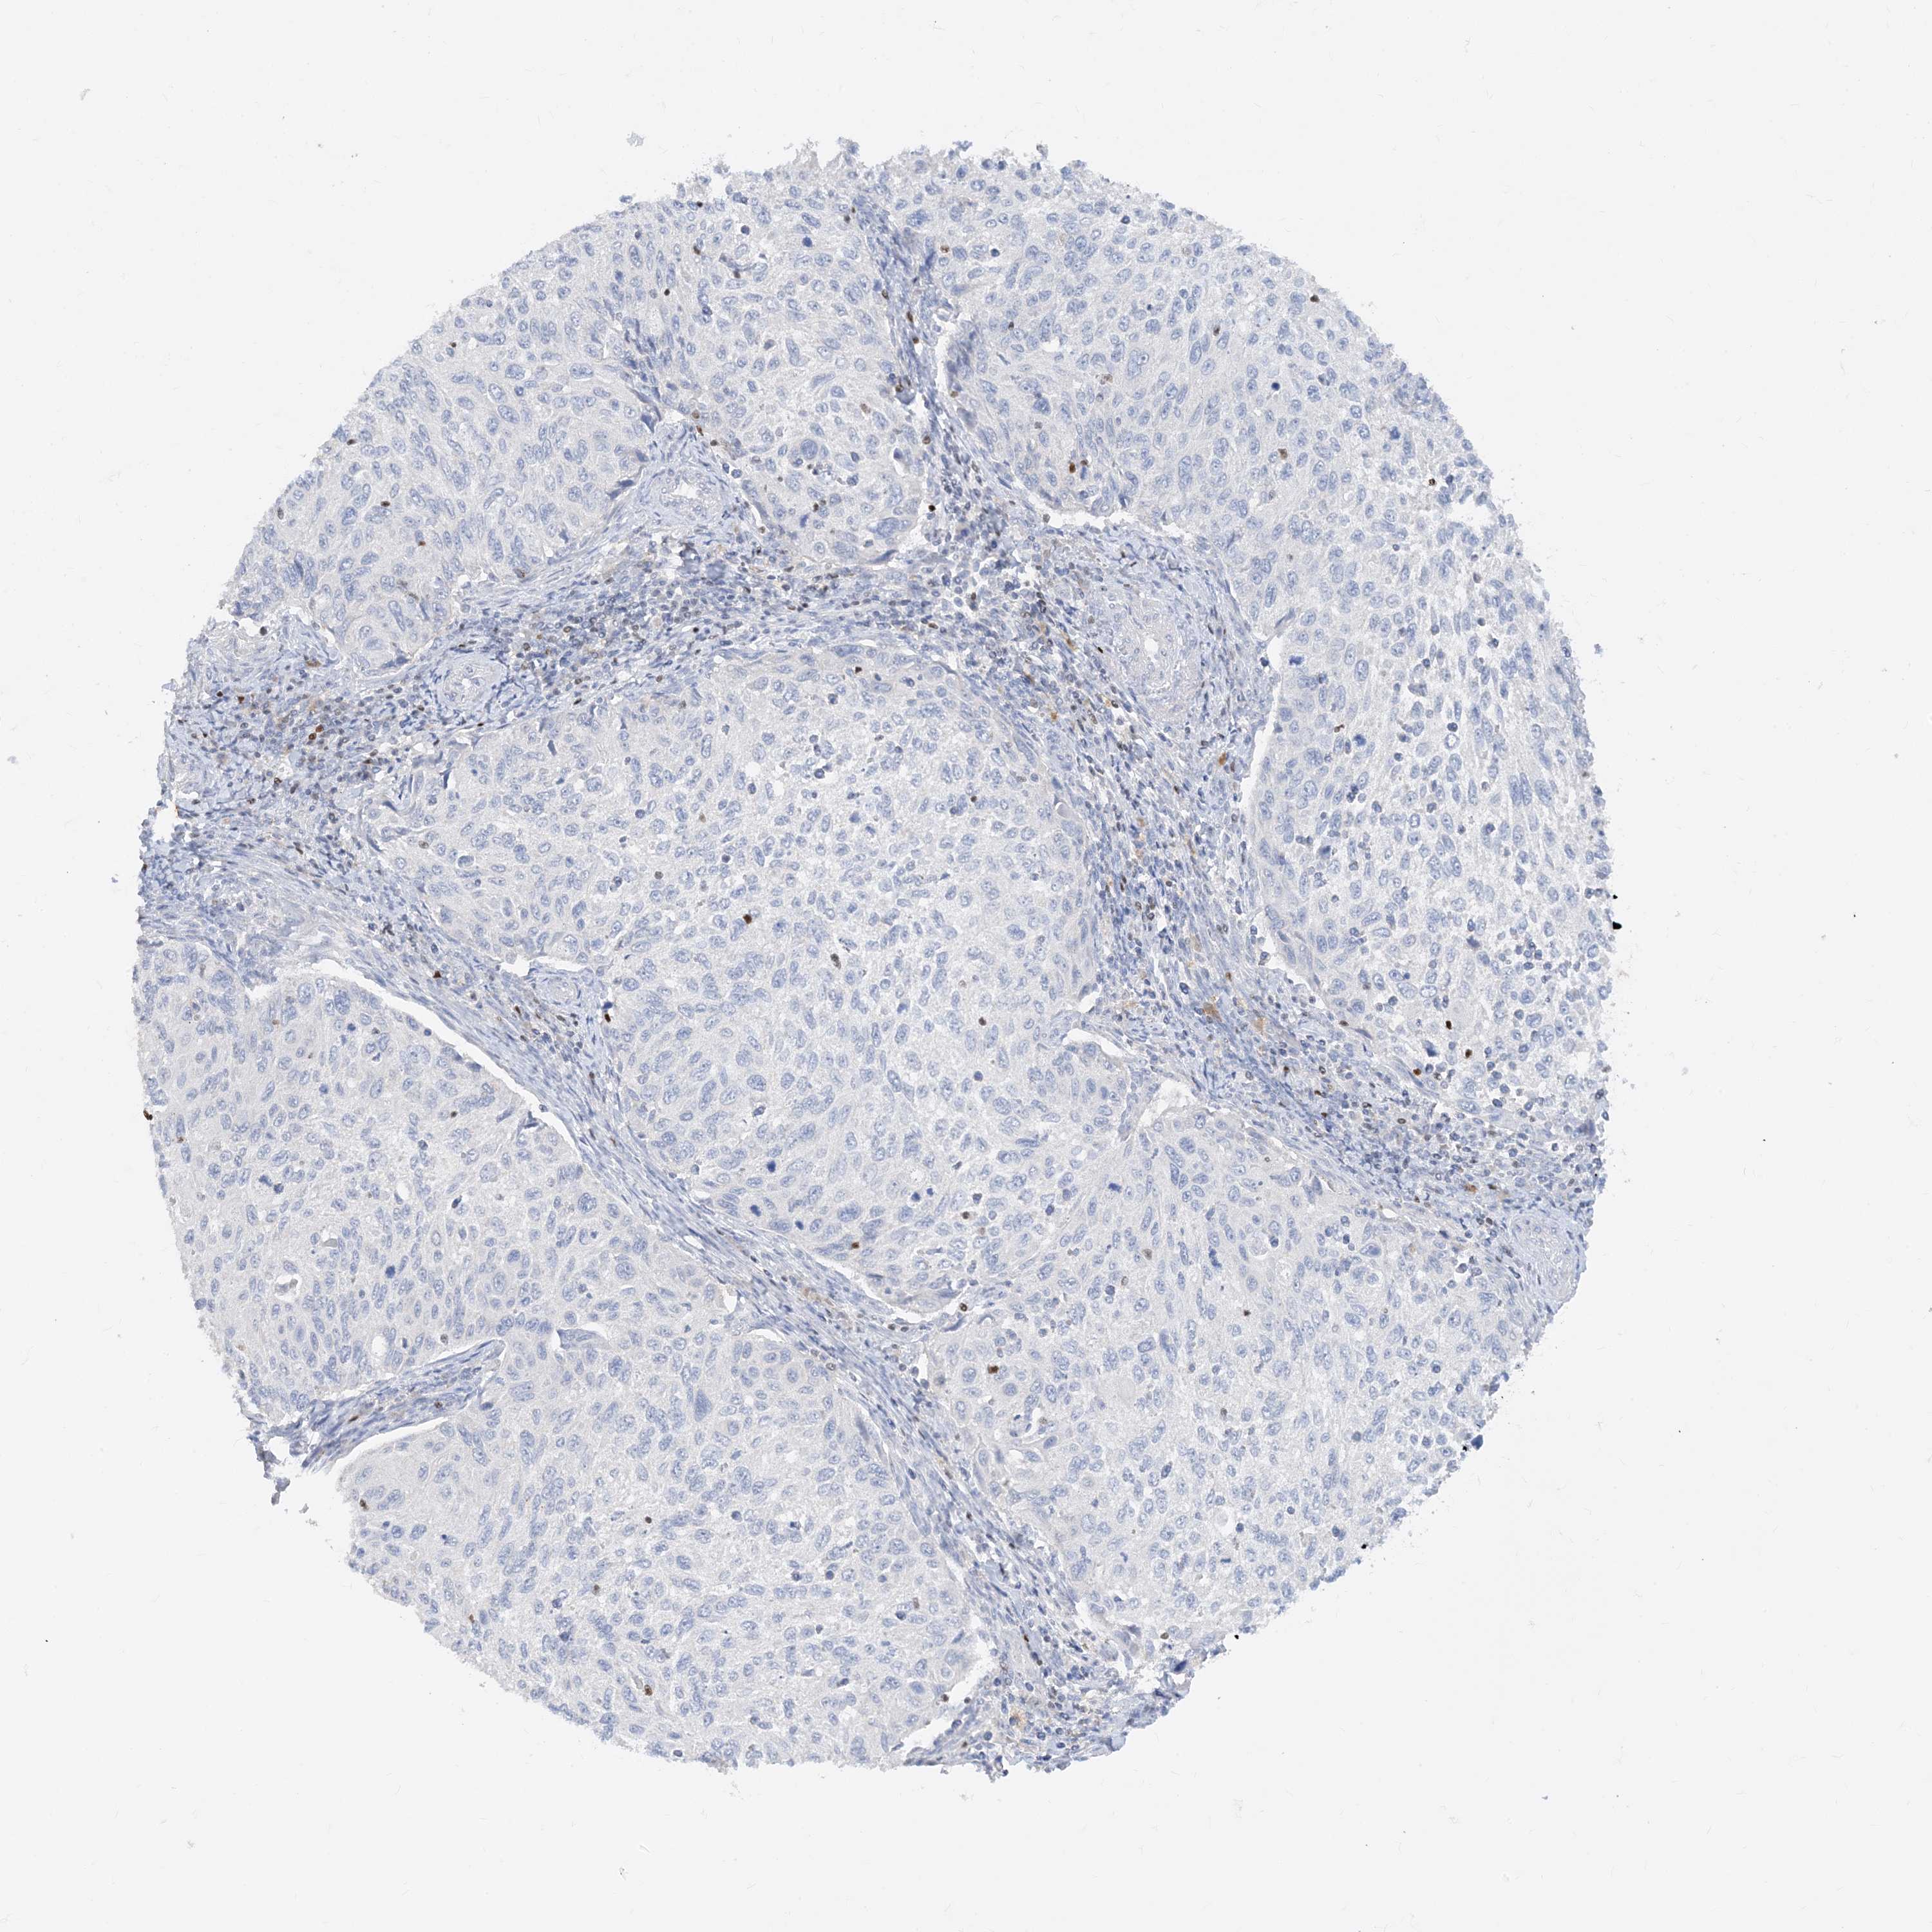

TBX21